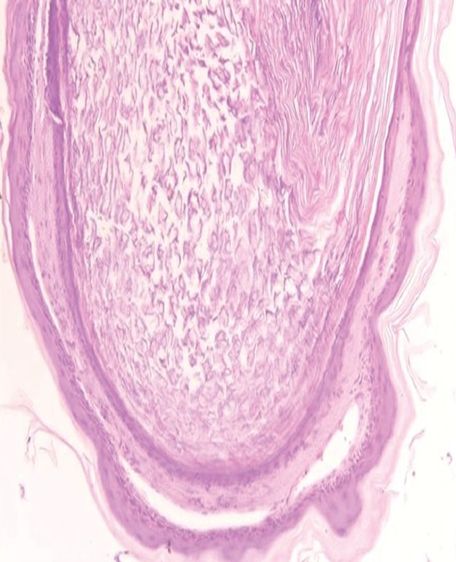

皮损于局部麻醉下切除,标本送病理检查。大体组织为囊状结构,含有软而臭的干酪样物质。镜下见囊壁有复层鳞状上皮和颗粒状细胞层,并含角质物,无附件结构(图2和图3)。

图3. 高倍镜示囊壁由复层鳞状上皮组成,包含颗粒层(HE染色,×250)